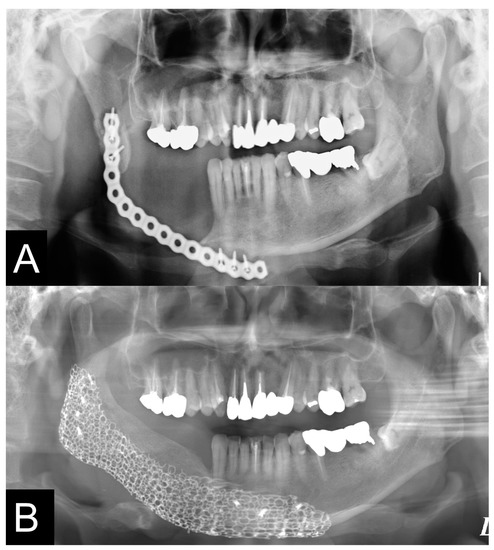

| 5 | F | 69 | SCC Gingiva | Surgical plate | Segmental bone defects | Ramus-body Class I | ![]() |

| 9 | M | 58 | Mucoepidermoid carcinoma Floor of mouth | Vascularized fibular bone graft | Segmental bone defects | Ramus-body-chin Class III | ![]() |